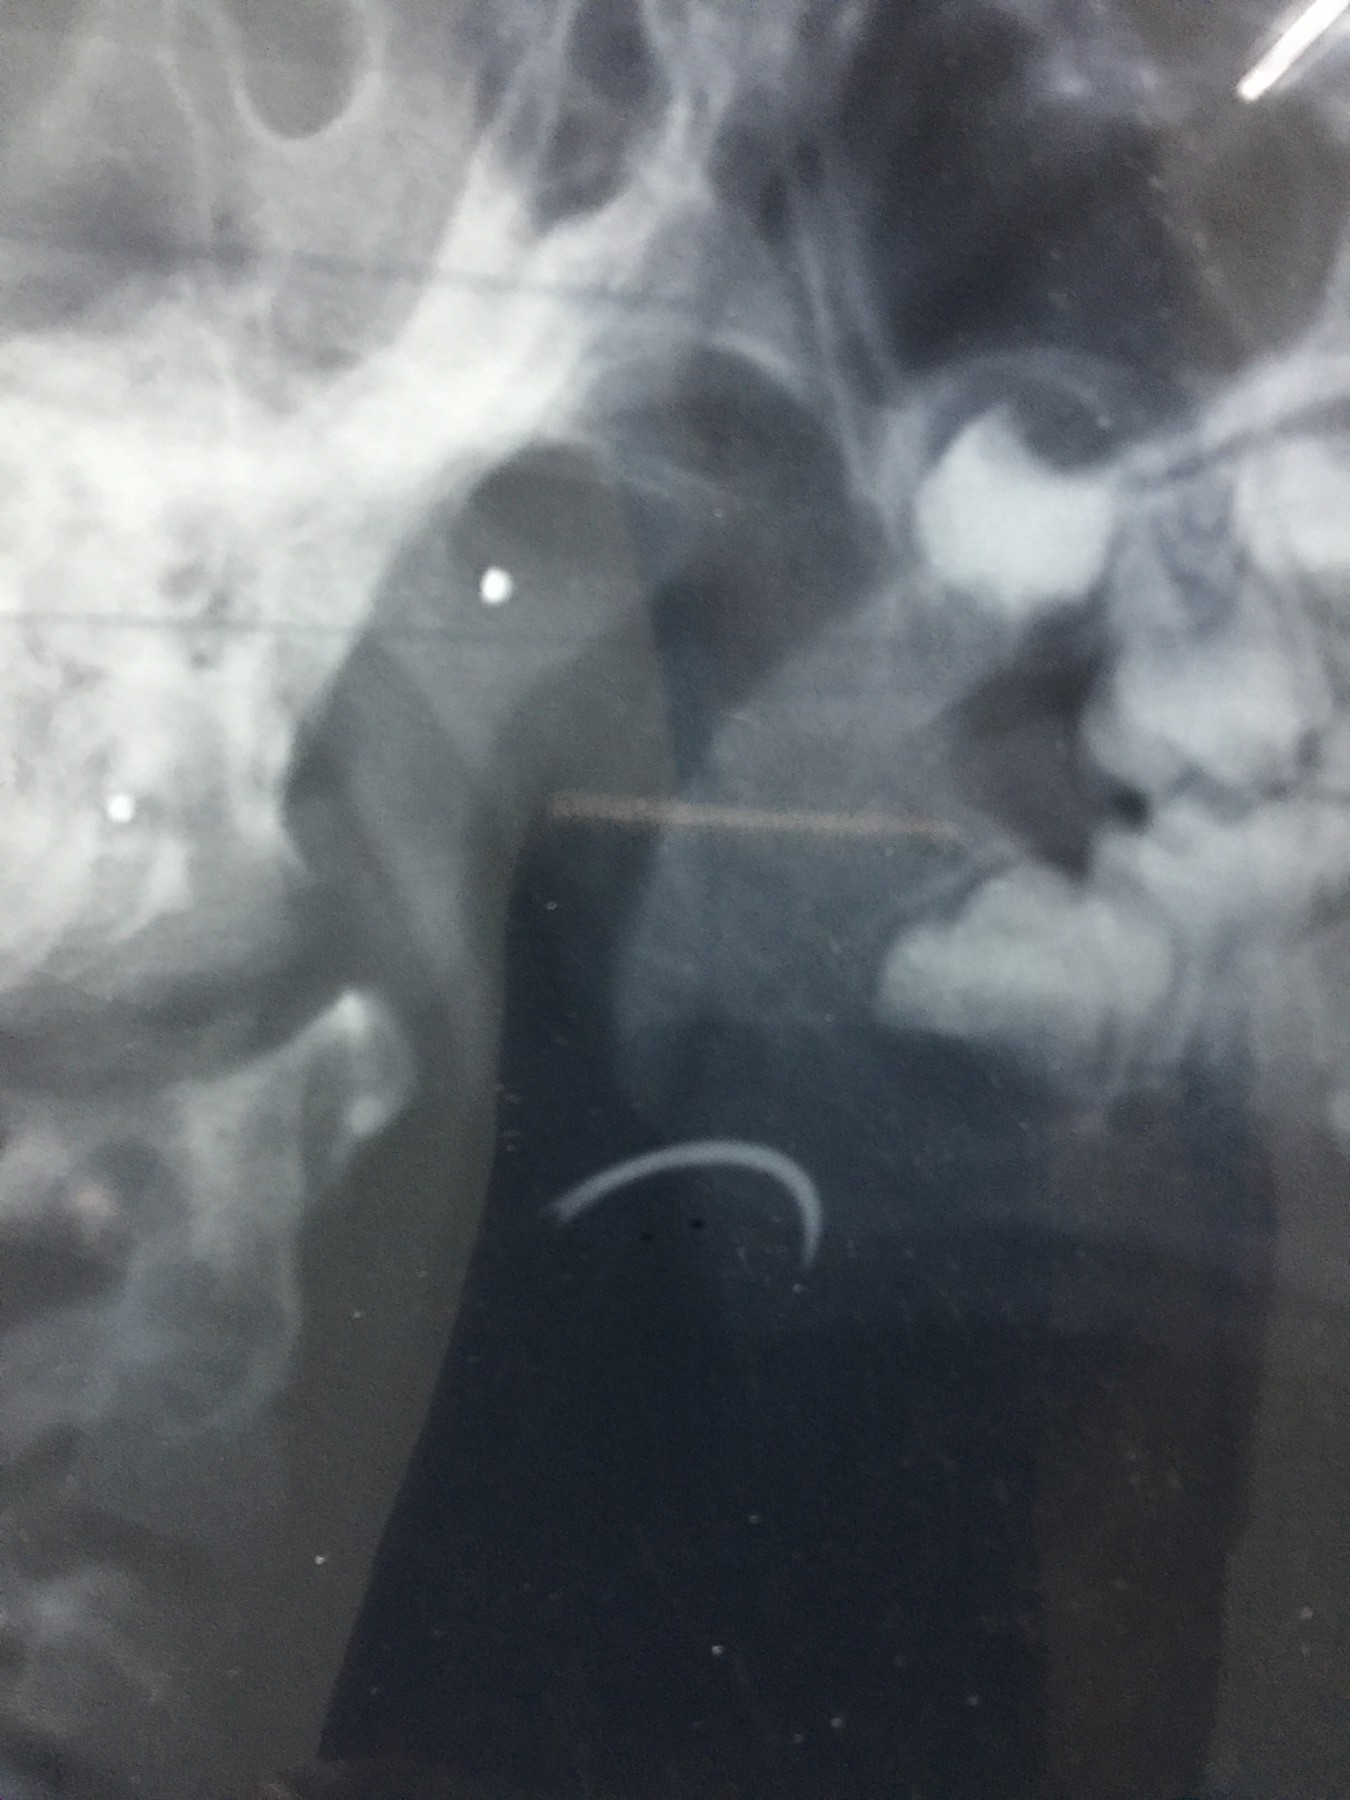

شهد مسلسل الإهمال الطبى حلقة جديدة بمستشفى جامعة طنطا، حيث نسى أحد الأطباء إبرة الخياطة الخاصة بالجروح داخل حنجرة أحد الأطفال خلال إجراء علمية جراحية لإزالة اللوزتين.

وأكد والد الطفل، أن الطبيب اكتشف أنه نسي الإبرة داخل زور نجله، وقام بتخدير نجله مرة ثانية لإخراج الإبرة ولكن دون فائدة، مؤكدا أن الطبيب أكد انه لن يستطيع استخراج الإبرة من الطفل.

وأكد، أنه توجه للدكتور أمجد عبد الرؤوف عميد كلية الطب، والدكتور هشام توفيق المشرف العام على المستشفيات الجامعية للتدخل لإنقاذ نجله، مشيرا إلى أنه تقدم بشكوى ضد الطبيب الذي أجرى العملية “أ.س” لرئيس قسم الأنف والأذن بالمستشفى، وعميد كلية الطب والمشرف العام على المستشفيات الجامعية، مؤكدا أن رئيس قسم الأنف والأذن والحنجرة، استدعى أطباء من خارج المستشفى لإنقاذ نجله، وأكدوا أن فى ذلك خطورة على حياته.